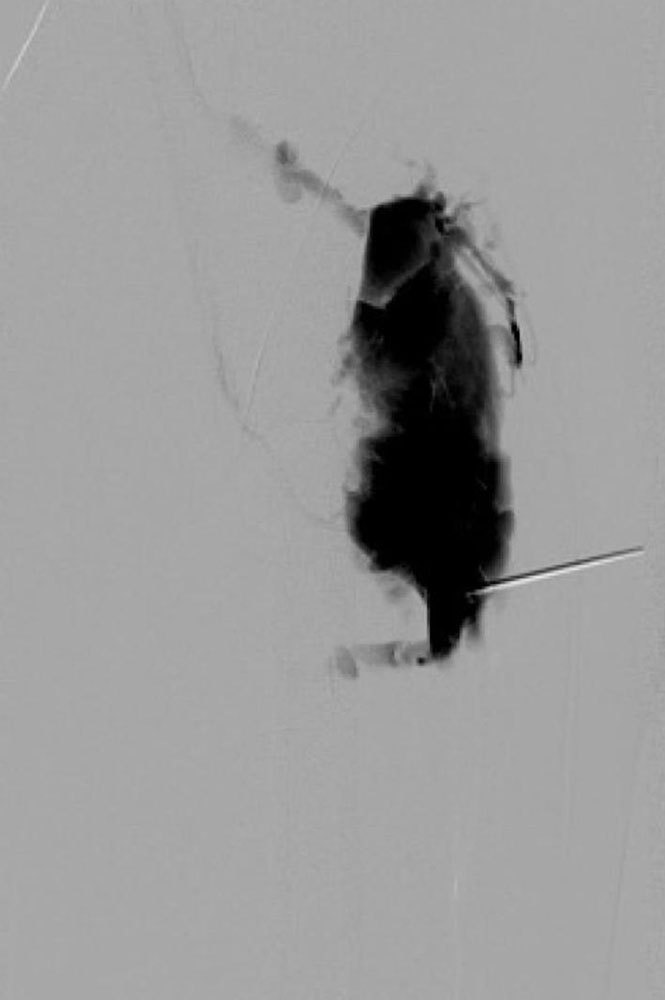

Sclerotherapy

This interventional therapeutic procedure is the method of choice in the treatment of venous malformations because of its relatively low invasiveness, its simplicity and its effectiveness. The injection of a sclerosing agent causes inflammation of the vascular endothelium, leading to obliteration of the venous malformation so that it can no longer fill with blood. Congestion and phlebitis can thus no longer occur. The resulting scarred connective tissue is inactive and remains in the body without any consequences. Large-lumen malformations with numerous branches require the repeated injection of large quantities of sclerosing agents. Several puncture sites and closely spaced treatment intervals are necessary to ensure that a sizeable area is sufficiently “dried out”. Otherwise there is a risk that an initially sclerosed venous malformation will re-open by reperfusion from neighboring regions (= real recurrence).

The more extensive the venous malformation, the more important the strategic approach is. It is not the easily accessible parts, but the parts causing symptoms or potentially leading to complications that must be addressed first. The combination of findings from physical examination and cross-sectional imaging provides the basis for this. It is helpful to let the patient mark the tissue areas on the skin that cause the most complaints. The underlying venous malformation represents the target tissue for the invasive therapy. Since puncture and sclerosing agents are painful, it is recommended that the procedure be performed under general anesthesia for children and adolescents. Treatments on the neck and face or with pure ethanol will often be performed under general anesthesia, even in adults. After safe intraluminal placement of the puncture needle, a few ml of an i.v. contrast medium are injected: this allows the spread, flow paths and flow dynamics to be recorded, communicating veins to be identified and the needle position to be verified.

The required amount of sclerosing agent, estimated by means of the CM injection, is injected through the same needle. In doing so, it is important to observe whether there is rapid CM passage into the healthy venous system and whether a relevant communicating vein can be identified. If this is the case (from experience in approx. 10% of cases), the injection must not take place because it could trigger a deep vein thrombosis. The communicating vein must then be closed. Depending on the depth, the needle can be placed under digital or sonographic control. The effectiveness of sclerotherapy increases when the vessels are bloodless, so the affected part of the body is elevated whenever possible. This is naturally easier on the extremities than on the trunk or face.